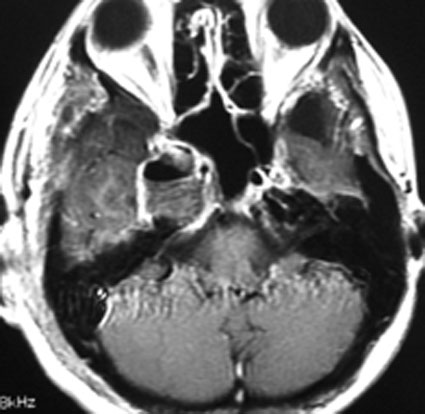

何も治療をしなくてもいい高齢者の三叉神経鞘腫,自然に小さくなります

これもメッケル腔(ガッセル神経節)という場所から発生した三叉神経鞘腫です。70代後半の女性に見つかったものです。左が2001年,右が2006年です。顔面の軽いしびれだけが症状で13年くらい経過観察していますが,大きくならないし,腫瘍の内部が壊死になってきています。何の治療もする必要のないものです。高齢者の三叉神経鞘腫は自然に小さくなること(自然退縮)があります。